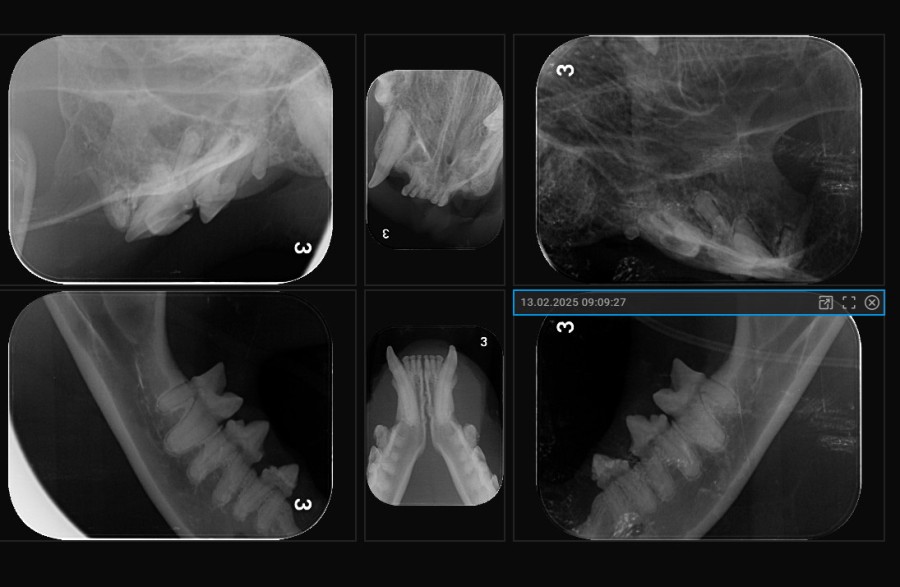

Dentalröntgen

Eine Zahnsanierung ohne Zahnröntgen ist medizinisch falsch. Mit unseren Zahnröntgengerät Scil 4DC und dem Röntgenfilmentwicklungsgerät IM3 CR7 sind alle Zahnwurzeln beurteilbar, um sicher sagen zu können, welcher Zahn gezogen werden muss.